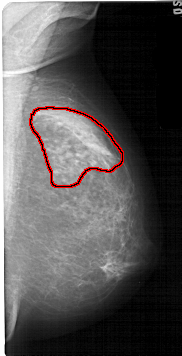

A_1599_1.RIGHT_MLO

RIGHT_CC LINES 5416 PIXELS_PER_LINE 2956 BITS_PER_PIXEL 12 RESOLUTION 43.5 OVERLAY

FILE: A_1599_1.RIGHT_MLO.OVERLAY

TOTAL_ABNORMALITIES 1

ABNORMALITY 1

LESION_TYPE MASS SHAPE ASYMMETRIC_BREAST_TISSUE MARGINS OBSCURED

ASSESSMENT 4

SUBTLETY 1

PATHOLOGY BENIGN_WITHOUT_CALLBACK

TOTAL_OUTLINES 1

BOUNDARY